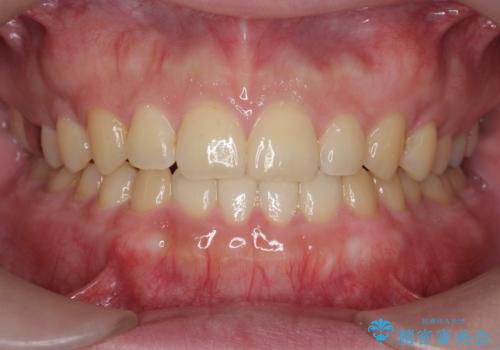

一度諦めた矯正にチャレンジしたい インビザラインとセラミック治療

少しだけ飛び出た前歯を整えたい インビザラインによる矯正治療

抜けてしまうと言われた前歯 インビザラインによる矯正治療

深いかみ合わせ 出っ歯の治療 インビザラインで

見た目だけじゃない:マウスピースでも短期間で噛み合わせと口元を改善

飛び出した前歯と黄ばんだ歯 ホワイトニングしながらマウスピース矯正

下の前歯が見えない:深い噛み合わせもインビザラインで

【モニター】前歯のデコボコをインビザラインできれいに整える

治療途中の前歯を治したい インビザライン矯正とオールセラミッククラウン

入国制限で帰国できず 海外出張中のインビザライン矯正

前歯のデコボコと突出感 インビザラインにて矯正治療

奥歯の銀歯と歯並びを改善 歯周外科治療と矯正治療を行った総合歯科診療